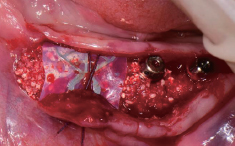

#46 발치와 부위에 시행한

Open membrane technique